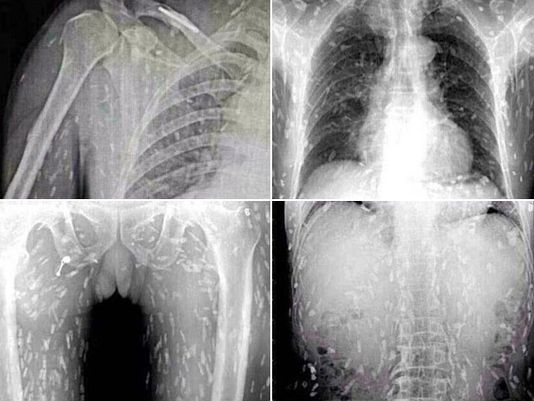

ชายจีนคอปลาดิบสุดช็อก ตรวจพบพยาธิแทรกซึมทั่วร่างกาย แพทย์เชื่อไข่พยาธิมาจากปลาดิบ

รายงานระบุว่า ชายจีนจากเมืองกวางโจว มณฑลกวางตุ้ง ซึ่งไม่ได้รับการเปิดเผยชื่อรายนี้ เป็นคนที่ชื่นชอบการทานปลาดิบเอามาก ๆ เขาทานปลาดิบเป็นประจำ กระทั่งวันหนึ่งเขาเกิดอาการปวดท้องและคันตามผิวหนังอย่างไม่ทราบสาเหตุ จึงรีบไปพบแพทย์เพื่อตรวจดูอาการที่โรงพยาบาลกวางโจว หมายเลข 8 ซึ่งเมื่อแพทย์เอกซเรย์ดูก็ต้องอึ้ง เมื่อพบว่าภายในร่างกายของเขามีแต่พยาธิตัวตืดเต็มไปหมด

จากเหตุการณ์ดังกล่าวแพทย์เชื่อว่าพยาธิเหล่านี้น่าจะมาจากการทานเมนูปลาดิบญี่ปุ่นที่ไม่สะอาดและมีไข่ของพยาธิ และจะเป็นอันตรายถึงชีวิตหากพยาธิลามถึงกระแสเลือดและสมอง